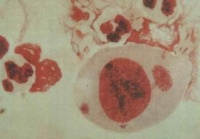

1 发育周期与形态染色 衣原体在宿住主细胞内繁殖有特殊生活周期,可观察到两种不同的颗粒结构:(1)原体(elementary body,EB)直径为0.2~0.4的小球形颗粒,有胞壁,内有核质核蛋白体,是发育成熟的衣原体,为细胞外形式。Giemsa 染色呈紫色,Gimenez 染色呈红色。原体具有高度的感染性,在宿主细胞外教稳定,无繁殖能力,通过吞饮作用进入胞内,原体在空泡中逐渐发育、增大成为网状体。(2)网状体(reticulate body,RB)或称始体(initial body),EB通过吞饮作用进入胞内,由宿主惜败包围EB形成空泡,并在空泡内逐渐增大为RB。直径为0.5~1.0μm,圆形或椭圆形。电子致密度较低,无胞壁,代谢活泼,以二分裂方式繁殖。RB为细胞内形式,无感染性,Macchiavello染色呈蓝色。RB在空泡内发育成许多子代EB也称为包涵体。成熟的EB从宿主细胞中释放,在感染新的易感细胞,开始新的发育周期,整个发育周期约需48~72h.